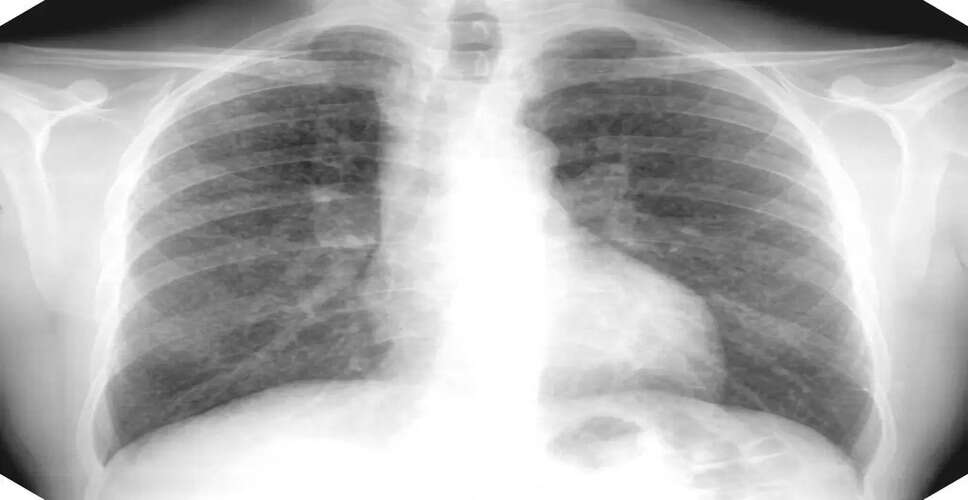

वर्ष 2021 तक सिलिकोसिस से पीड़ित लोगों के प्रमाण पत्र ऑनलाइन किए जाते थे। संबंधित चिकित्सकीय जांच के बाद प्रमाण पत्र भी बनवाए गए। इसके बाद इन्हें ऑनलाइन किया जाने लगा। अब सबसे पहले ई-मित्र पर ऑनलाइन आवेदन करना होगा। फिर मरीज के एक्स-रे के आधार पर संबंधित ब्लॉक के डॉक्टर तय करते हैं कि वह व्यक्ति सिलिकोसिस से पीड़ित है या नहीं। ब्लॉक या जिला स्तर पर जांच के बाद सिलिकोसिस के मरीजों का एक्स-रे किया जाता है। उसी के आधार पर बीमारी की पहचान की जाती है। फिर उस एक्स-रे को जयपुर भेजा जाता है, जहां एक्स-रे देखकर यह तय हो जाता है कि मरीज सिलिकोसिस से पीड़ित है या नहीं। दाेसा से भेजे गए 88 एक्स-रे के आधार पर इसे सिलिकोसिस रोग नहीं माना जा रहा है।

जिले में कुल 88 लोगों को संदिग्ध माना गया है, जिनमें सबसे अधिक 34 लोग महवा के हैं. दूसरे नंबर पर सिकराय प्रखंड है, जहां सिलिकोसिस से पीड़ित 27 लोगों को देखते हुए की गई एक्स-रे रिपोर्ट संदिग्ध मानी जा रही है. दाइसा में 11, बांदीकुई में 14 और लालसात प्रखंड में सिर्फ 2 लोग हैं. इन सभी लोगों से अब दोबारा पूछताछ की जाएगी। सभी को मेडिकल बोर्ड के सामने पेश होना होगा। इसके बाद उनका ताजा एक्स-रे किया जाएगा। इसके बाद ही यह तय हो पाएगा कि कैन-कैन वास्तव में सिलिकोसिस से पीड़ित हैं। इसमें सरकार की ओर से पीड़िता को पालक योजना का लाभ देने के साथ ही रु. 1500. पेंशन भी मिलती है।